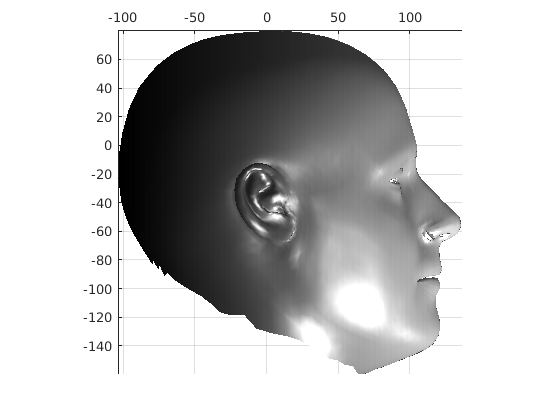

Following this, OSNR ICP iterates over a set of decreasing mesh stiffnesses (typically 10), until the registration between the template and the scan is below some error or a maximum number of iterations is reached. Figure 28 shows a selection of template warp results. The template appears to be accurately warped onto the scan, at least in the normal direction of the surfaces, it is not possible to see error tangential to the surface. Furthermore, we have noted errors on some scans on the ears. To improve these we need a method of automatically landmarking the ears, which is an area for further work.

|

|

|

|

|

|

|

|

The first two modes of head variation are shown in figures 29 and 30. These include the cranial height / facial angle mode and the (almost) pure size mode, as seen in the sagittal profile model.